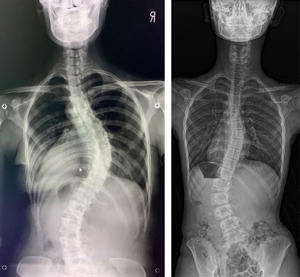

側弯症:こどもの側弯症、大人の側弯症

子どもの側弯症

どんな病気?

せぼね(脊椎)は7個の頚椎、12個の胸椎、5個の腰椎と仙椎から構成されます。正常な状態では脊椎は正面から見ると真っ直ぐです。一方側弯症では正面から見た時に椎体がねじれ(回旋)を伴いながら、脊椎が左右に曲がっている状態です。側弯症の発生頻度は、装具治療の対象となる20-30度度以上の側弯症はおおよそ0.3~0.5%と報告されています。手術が必要な可能性が出てくる40度以上の側弯はおおよそ0.1%です。

原因

こどもの側弯症には様々な原因があります。一番頻度の高いものは特発性側弯症です。特発性とは「原因が現時点で不明である」という意味です。特発性側弯症の原因を世界中で研究されていますが、今のところはっきりとした原因は分かっておりません。特に思春期の女児に多いことがわかっています。そのほかの側弯症として脊髄などの中枢神経の異常に伴う側弯症(神経原性側弯)、筋肉の疾患に伴う側弯症(筋原性側弯症)、椎体の変形による側弯(先天性側弯)、そのほかマルファン症候群などの結合組織の異常に伴った側弯症など、様々な側弯症の原因が分かっております。

症状

側弯症では脊柱が曲がってくるため、以下のような外見状の変化が生じる場合があります。

1.肩の高さの非対称

2.腰のくびれの非対称

3.骨盤の傾き

4.肩甲骨部の背中の出っ張り

特に最も多い胸椎が右に弯曲する側弯症ではアダムステストと呼ばれる体幹を前に屈めるテストを行うと、右の背中が盛り上がります。痛みや機能の障害を伴うことは比較的稀です。

治療法

こどもの側弯症の治療法は側弯の程度に応じて以下のように分けられます。

1.経過観察

3-12ヶ月毎にX線を撮影して側弯の進行を確認します。このような場合はカーブの大きさがコブ角で25度以下の軽度の側弯症の場合です。

2.装具治療

骨成熟前(おおよそ14-15歳以下)でコブ角が25度前後の場合に開始します。装具は、初期には一日中着用します。おおよそ16歳前後まで着用します。装具治療開始後は3-4ヶ月毎にレントゲンを撮り、カーブの進行の有無を確認します。装具は個人ごとに最も側弯の矯正に見合った形に型取りをしてオーダーメイドで作成します。近年の米国での信頼性の高い研究でも長時間の装具の着用が側弯症の進行の予防に効果的であることが報告されています。

3.手術療法

手術の最大の目的は側弯の進行の予防です。進行の確率は、10~12歳の場合、コブ角30度以上の側弯では約90%の確率で、コブ角60度以上の側弯の場合は100%の確率で進行します。仮に重度の側弯症になった場合、疼痛や整容的な問題にとどまらず、肺機能の低下(息切れ)が生じます。これは脊柱の変形によって肺が圧迫されるためです。骨の成長終了後(18-20歳以上)もコブ角が40度を超えた側弯症は年間0.5~1度程度の進行があるといわれております。成長終了後の側弯症では、今後の側弯の進行の可能性と手術の危険性などを主治医と相談して、手術を受けるかどうか決めたほうが良いと考えられています。